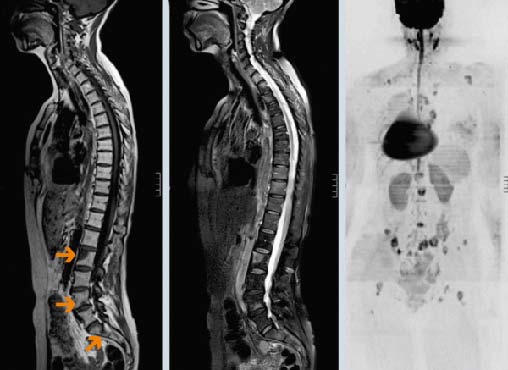

Основные методы диагностики — КТ и МРТ. Они позволяют детально визуализировать структуры позвоночника и опухолевую ткань. Рентгенография менее информативна, так как показывает только костные структуры и обычно используется при подозрении на патологический перелом.

Диагноз подтверждается биопсией. Врач получает фрагмент опухолевой ткани и отправляет его в лабораторию для цитологического и гистологического исследования, а также молекулярно-генетических анализов. Материал для биопсии может быть получен различными способами:

- Чаще всего проводят пункционную чрескожную биопсию с помощью иглы под контролем рентгена.